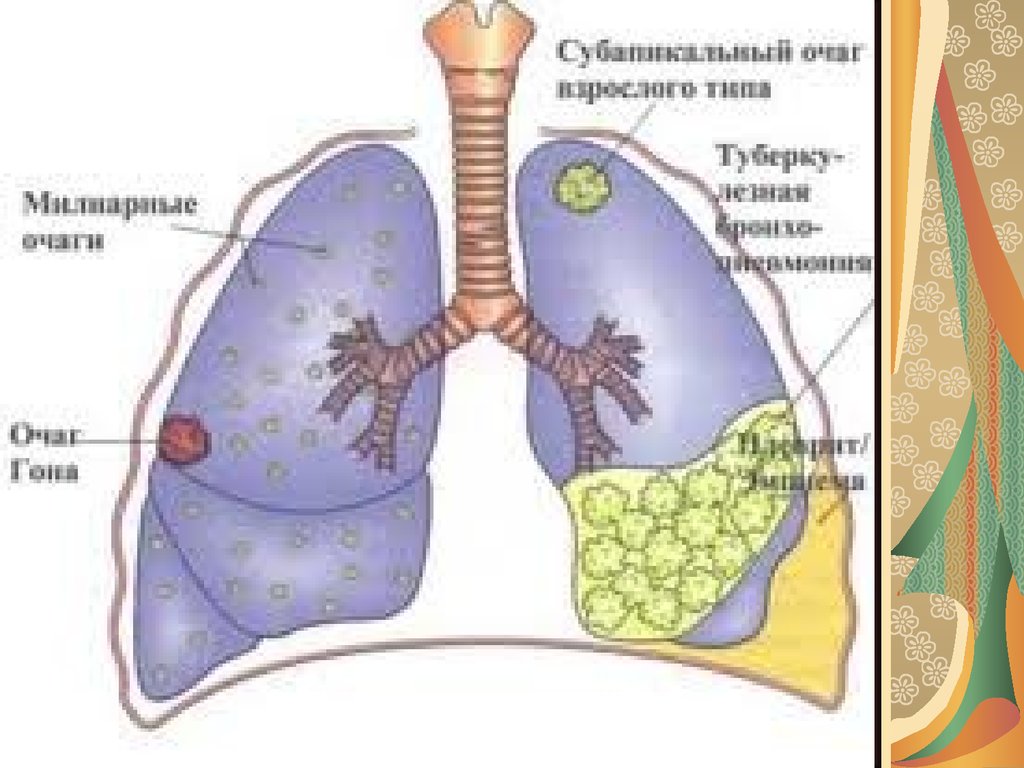

Симптомы и признаки туберкулеза: как распознать заболевание

Раздел: Визуальные уроки